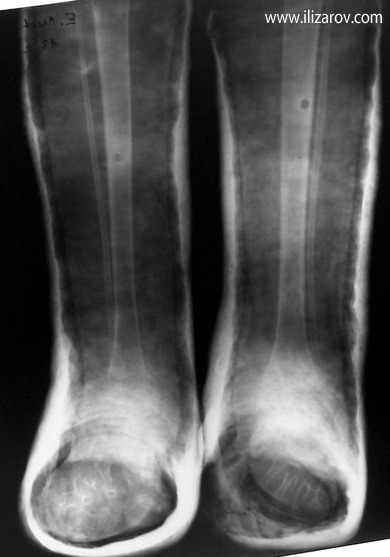

Case 4